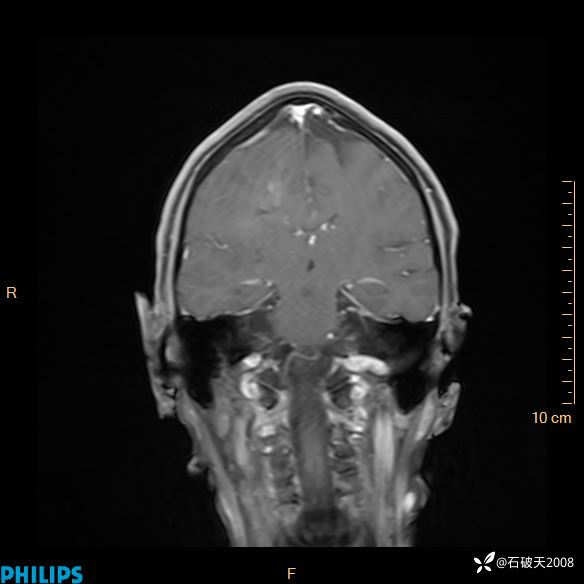

2024.2.21MR

增强冠状位